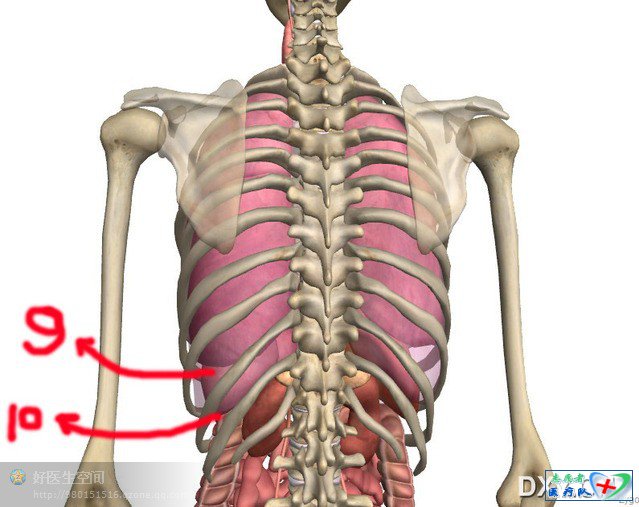

记住,正确的pose应该这样摆,当然你会说拍片位置角度本身就千差万别,这个就跟学心电图一样,你不能说人的体型千差万别你的心电图胸导就可以随便放吧,现在开始数骨头,数一数胸椎,数一数肋骨,拍的好的胸片胸锁关节平面正对第三胸椎,左右锁骨是对称的,看片是一眼看去先看这个这是个很重要的小技巧

我们熟悉的肝上界是第五肋间隙吧就是锁骨中线上膈肌顶端 (顺便复习下肺下界在锁骨中线、腋前线、肩胛下线是6、8、10肋间这个在胸水定位中也很重要),我接着上图,各位有兴趣接着数骨头

后的一些标志,注意拍片室肩胛骨是打开的,但我们抽胸水是肩胛骨可以用到,肩胛骨下缘多数是在第7肋间隙(肩胛下线)

我们所说的肺下界平静呼吸时在肩胛下线是第10肋间,前面提过,但是注意其实我们扣得应该是整个膈肌以上胸腔下缘,真正肺部伸不到那儿,要高一点,这一点教材没提到,在抽胸水时要理解